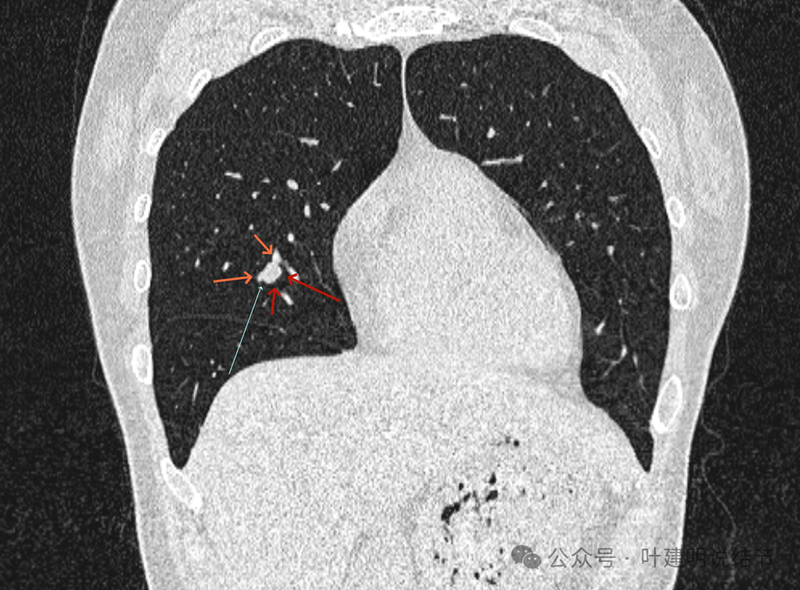

再看冠状位影像:

血管与病灶的关系,两者密度稍不同,天蓝色细箭头所指是分界线。

血管征明显。

血管围着病灶,病灶有膨胀性,表面欠平滑。

不而有膨胀性,血管贴着并被压迫。

边缘欠平滑,邻近血管间隙欠清晰。

血管贴着,结节膨胀。

也示血管与病灶的关系。

结节实性。

纵隔窗这个角度明显见到蓝色箭头所指的血管被病灶侵蚀,而且血管与病灶密度的不同。